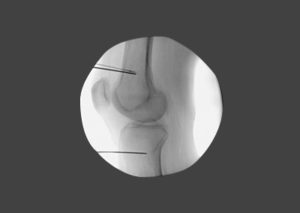

Pain specialists, Pain management specialists, Spine specialists, spine surgeons and patients are always looking for long-term solutions rather than short-lived interventions for their pain. There are three main nonsurgical treatments to ablate nerves elements. These are; the use of extreme cold (cryoablation), high temperature radiofrequency and chemicals (neurolysis), such as alcohol or phenol. Radiofrequency ablation offers the advantage of being precise, reproducible and effective to a greater extent. It also has the ability to check before the ablation to avoid ablating the wrong nerve elements, which provides a considerable safety margin. Radiofrequency Ablation (RFA) is a very exciting method in pain medicine that uses a specialized device to disrupt nerve’s role of carrying the message of pain. A probe is inserted through a needle like instrument and controlled delivery of heat is placed along a painful nerve. RFA causes nerve destruction through heat. Interestingly this technique doesn’t alter other normal tasks of these nerves. One alternative technique, though less effective, Pulsed-RFA does not cause nerve destruction, but instead is used to stun painful nerves.